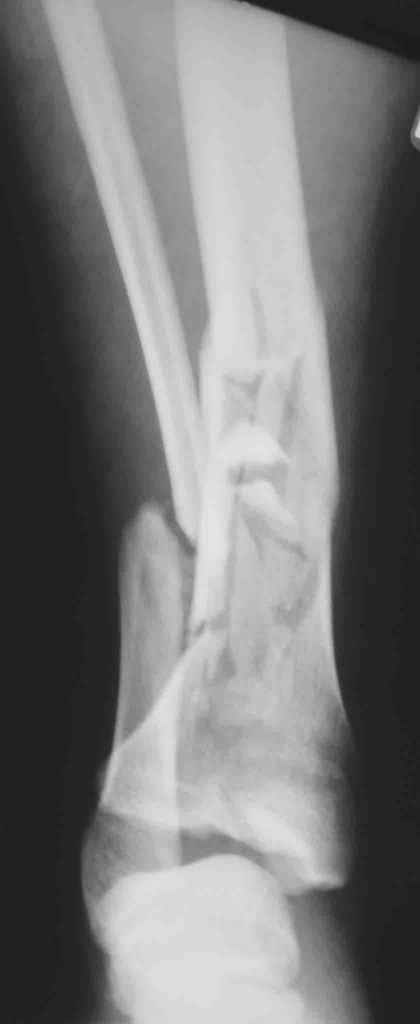

Re: Открытый оскольчатый внутрисуставной перелом дистального отдела большеберцовой кости

Вот что получилось

7.jpg

27KB (28411 bytes)